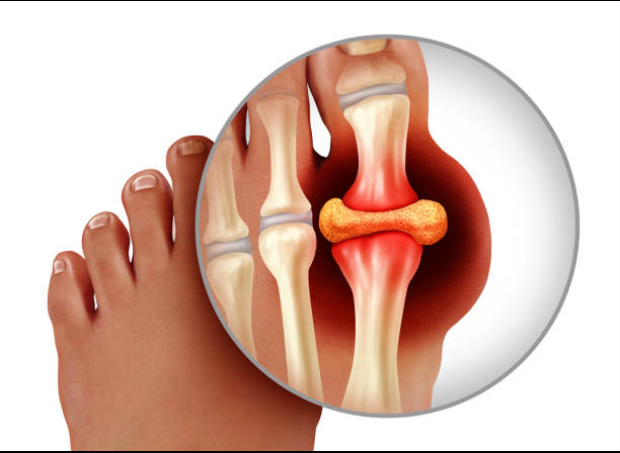

통풍이 있으면 다리를 절단하고 싶을 정도로 통증이 심합니다. 그리고 치료하지 않고 방치한다면 말기 신부전, 뇌졸중 또는 심근경색과 같은 생명을 위협하는 결과를 초래할 수 있습니다. 통풍은 요산으로 물질이 체내에 축적되어 관절염, 심한 통증, 신장 기능 장애를 일으키는 질환입니다.

그 후, 손, 무릎, 발목의 관절에 계속해서 영향을 줄 수 있습니다. 통풍의 증상은 시기에 따라 고요산혈증, 급성 통풍성 관절염, 간헐성 통풍의 3단계로 분류할 수 있습니다. 일반적으로 엄지발가락 관절의 갑작스러운 종창이 처음 징후이며, 곧 해당 부위에 극심한 통증과 발적이 뒤따릅니다. 관절이 뜨거워져 신발을 신을 수 없게 될 수 있습니다. 그리고 손, 무릎, 발목의 관절에도 연속적으로 영향을 미칠 수 있다.

통풍이 진행된다면 10일 정도 지속되며 완화되더라도 재발하거나 악화될 수 있으므로 치료를 받아야 합니다. 급성 통풍성 관절염은 보통 엄지발가락에 나타나지만 발 관절, 발목, 무릎, 심지어 손목에도 영향을 미칠 수 있습니다. 간헐성 통풍은 일반적으로 6개월에서 2년 사이에 2번째 발작을 일으킵니다. 통풍 발작을 치료하지 않으면 시간이 지남에 따라 여러 관절로 전이될 가능성이 높아지므로 반드시 치료를 받고 정상적인 요산 수치를 유지해야 합니다.